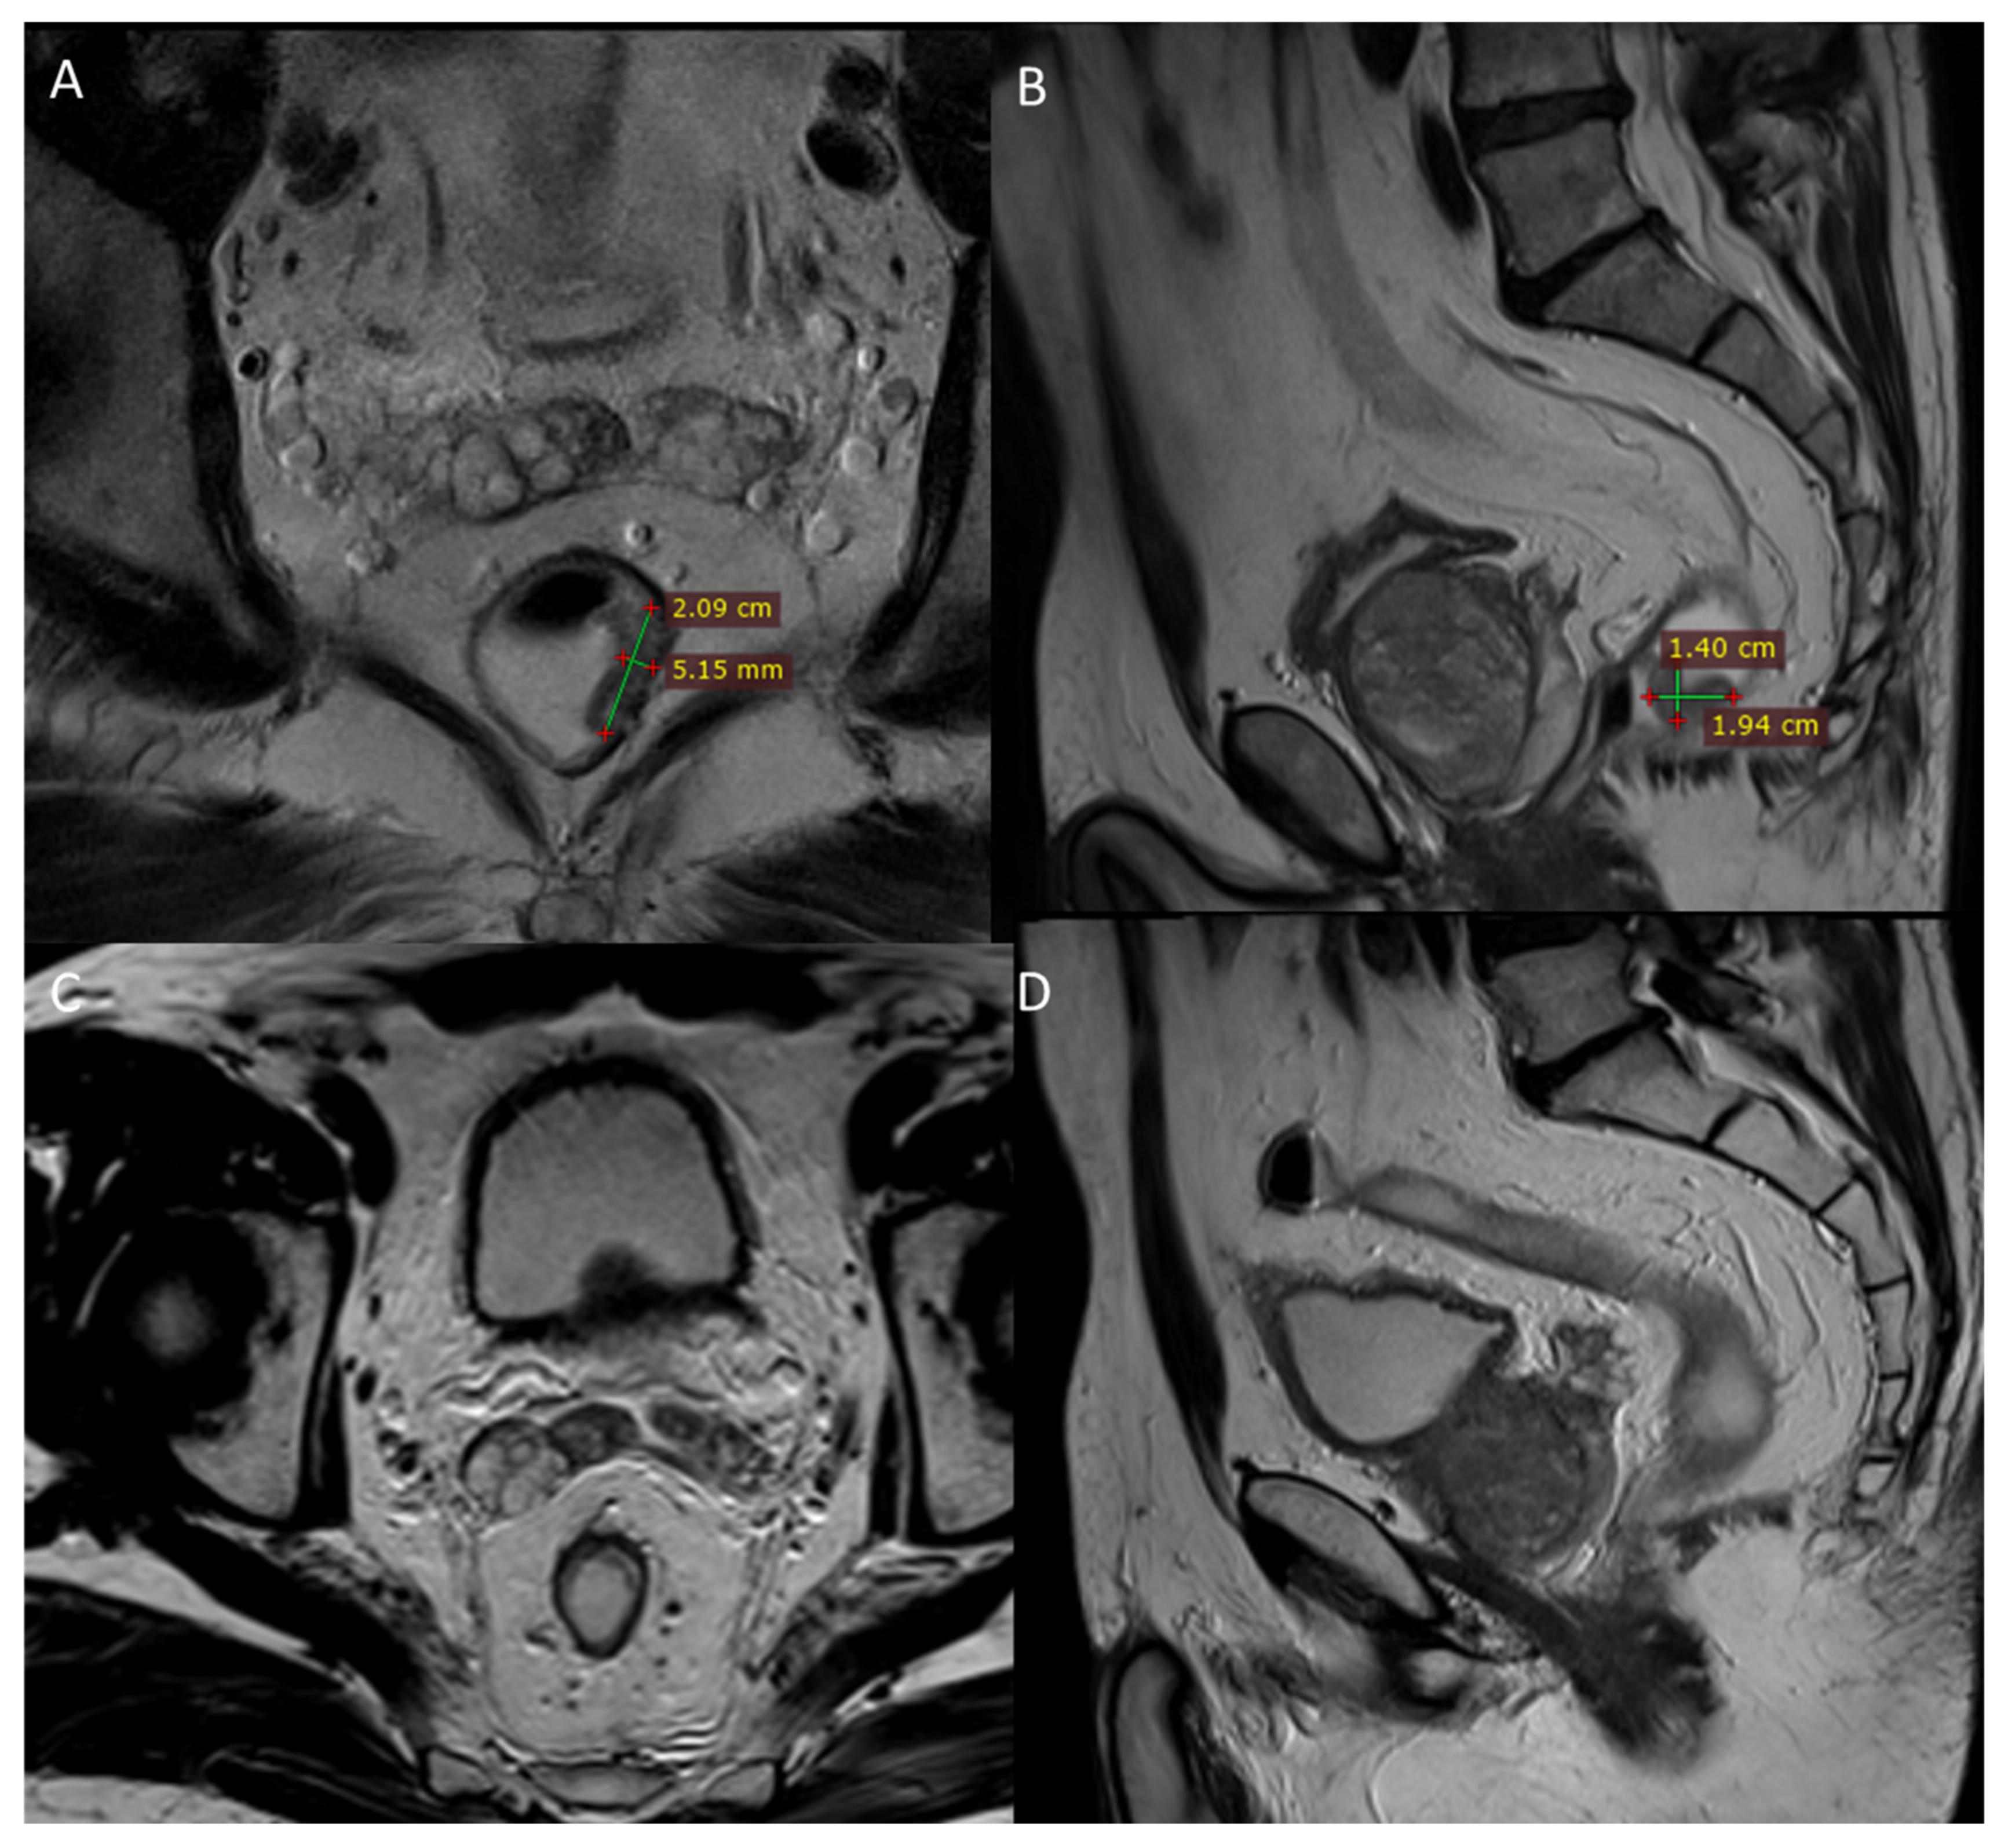

2.4. Third LARC Case Description

| 3 | Male 50 years old with recurrence after long course neoadjuvant therapy and total mesorectal excision (TME) treated with ECT | Variable and fixed geometry electrodes | MRI 6 months after ECT treatment showed no significant morphostructural changes in the lesion that was considered to be stable disease. Patient reported a reduction in pain on the VAS 7 to 4 scale and a reduction in bleeding. |